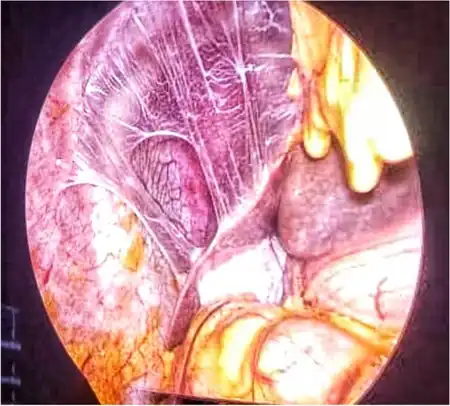

| Perihepatic adhesions | |

The gold standard for diagnosis of Fitz-Hugh–Curtis syndrome, though rarely required, is laparoscopy with direct visualization of the characteristic "violin string adhesions" along with liver capsule scarring and inflammation. Antibody testing of 57-kDa chlamydial heat-shock protein can be done in cases where all other tests have been non-diagnostic and the clinical suspicion remains high.[14]

The condition is named after the two physicians, Thomas Fitz-Hugh Jr. and Arthur Hale Curtis, who further studied the syndrome in the 1930s. They noted the classic "violin string adhesions" in female patients presenting with RUQ abdominal pain. Both Fitz-Hugh and Curtis regularly found these adhesions during laparotomy in patients with the clinical syndrome of RUQ with concern for gallbladder pathology; however, no abdominal pathology was found in these patients but residual gonococcal tubal changes were often noted.[24][25]